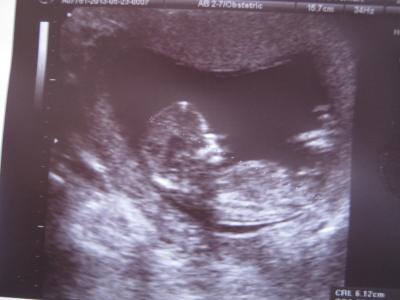

So, bin wieder da. Nackenfalte ist unauffällig (1,2 mm) Mäuschen ist 6,1 cm groß bei 13+1 und auch ansonsten ist alles da wo es sein soll. Jetzt muss ich noch bis nächste Woche Freitag warten, dann gibt es die Blutergebnisse usw. Hier das neue Bildchen:

Bild zu Babyfoto :) - Forum für November - Mamis